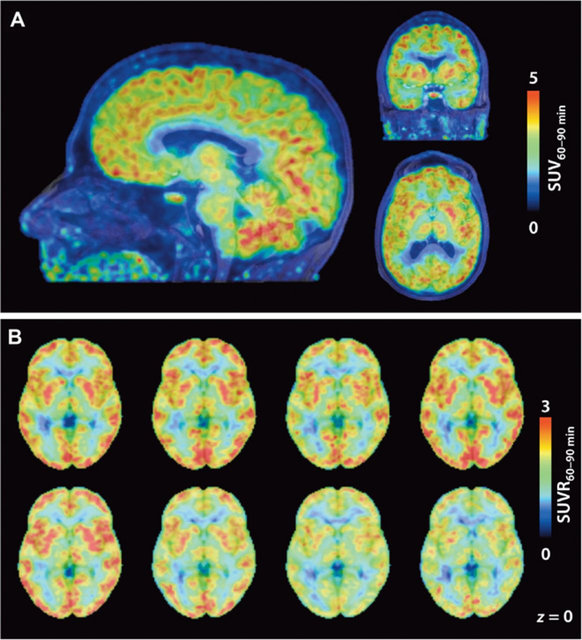

پس از اتصال این ترکیب به " HDACs" دانشمندان توانستند فعالیت مولکول‌ها را با استفاده از اسکن PET در مغز افراد مشاهده و پیگیری کنند. این کار به محققان نشان می‌دهد که این مولکول‌ها در کدام قسمت از مغز هستند.

نتایج این آزمایشات نشان دادند که سطوح "HDAC" در مخچه که کنترل عملکرد حرکتی را بر عهده دارد بالا بوده و در ماده سفید بسیار پایین‌تر است. اما هنوز هم اولین گام این نسخه از Martinostat"" تنها با سه نوع از یازده نوع HDAC"" متصل شده و فعالیت هشت نوع دیگر هنوز نامشخص است.